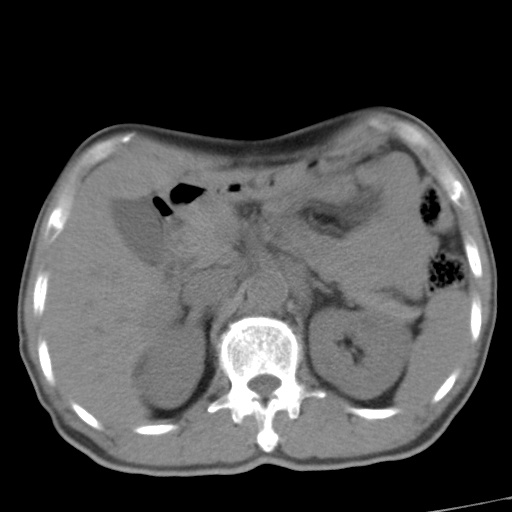

标题: CT17975:请求会诊。男、57岁。上腹部胀痛2天。临床诊断:糜 [打印本页]

标题: CT17975:请求会诊。男、57岁。上腹部胀痛2天。临床诊断:糜

肝脏多发类圆形低密度影,考虑肝脏转移瘤,肝胃韧带一淋巴结肿大,原发?胃癌?

肝内转移瘤,腹腔及腹膜后淋巴结转移。